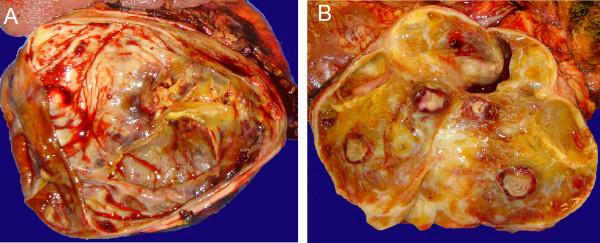

Three female patients with retroperitoneal ancient schwannomas were reviewed. One patient presented with several weeks of upper abdominal pain and lower chest discomfort, whereas back pain and leg pain with associated weakness were predominant symptoms in the remaining two. Abdominal imaging findings demonstrated heterogeneous masses in the retroperitoneum with demarcated margins, concerning for malignancy. The patients successfully had radical excision of their tumors. Histological examination showed encapsulated tumors that displayed alternating areas of dense cellularity and areas of myxoid matrix consistent with a diagnosis of ancient schwannoma.

回顾了三例患有腹膜后陈旧性神经鞘瘤的女性患者。一名患者出现数周的上腹部疼痛和下胸部不适,而另外两名患者的主要症状是背痛和腿痛并伴有相关的无力感。腹部影像学检查发现腹膜后有边界清晰的异质性肿块,怀疑为恶性肿瘤。患者均成功地进行了肿瘤根治性切除。组织学检查显示肿瘤有包膜,呈现出密集细胞区域和黏液样基质区域交替出现的情况,符合陈旧性神经鞘瘤的诊断。